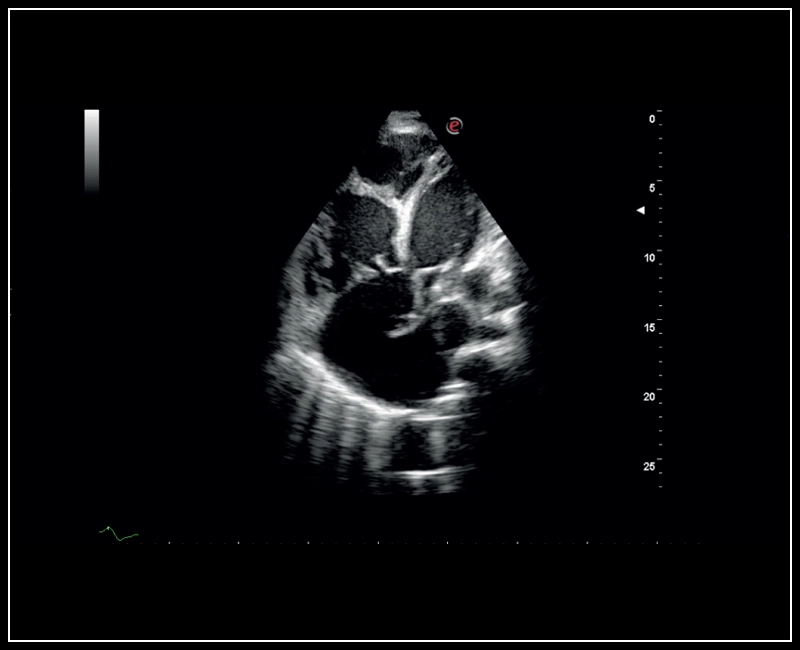

Q7 - CV Cardio B-mode

Q7 - CV Cardio B-mode

Q7 - CV Cardio B Mode 2

Q7 - CV Cardio B Mode 2